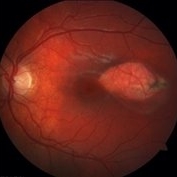

Fundus photograph of an asymptomatic 12-year-old girl with torpedo maculopathy of the left eye.

Photographer: Pierre-Henry Gabrielle, Ophthalmology department, Dijon University Hospital, France

Imaging device: Zeiss visucam

Condition/keywords: fundus photograph, torpedo maculopathy